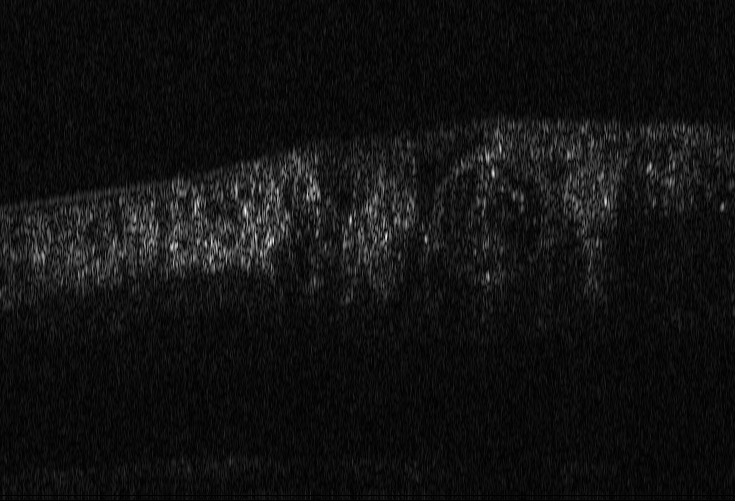

We use here representative image data obtained using an adaptive optics (AO) supported spectral domain OCT system (citep \@BBN(Brunner et al., 2021)). Cross-sectional images (B-scans) were retrieved from two AO-OCT volumes recorded in a young healthy volunteer (27 years, female, right eye) with a field of view of approximately 4×4superscript4superscript44^{\circ}\times 4^{\circ} (corresponding to  1.4×1.4mm1.41.4𝑚𝑚1.4\times 1.4mm on the retina). Different imaging locations and focus settings were considered. One data set was recorded in the fovea with the focus of the imaging beam set to the posterior retina and one data set close to the optic disc with the focus shifted to the anterior retina. An algorithm including dispersion compensation and geometrical corrections was employed (citep \@BBN(Shirazi et al., 2020)) for the reconstruction. The images are shown on a linear intensity grey scale. The reference images, (a) in Figure 9 and 10, were obtained by manually optimizing over the parameters that define the compensation of dispersion, rotation and curvature, respectively. The examples in Figure 9 and 10 compare the chosen reference to three sub-optimal reconstructions, where (b) had a bad choice for the rotation correction parameter, (c) for the curvature correction parameter and (d) for the dispersion compensation parameter.

(b) (26.88, 0.71, 0.05)

Refer to caption

(c) (26.84, 0.72, 0.04)

(d) (29.94, 0.77, 0.06)

Figure 9: OCT reference reconstruction (a) and reconstructions with sub-optimal parameters (b)-(d) leading to geometric deviations (b)-(c) and low resolution (d). Here, (d) is wrongly judged as best reconstruction by SSIM and PSNR, LPIPS is able to ignore the small spatial deviations.